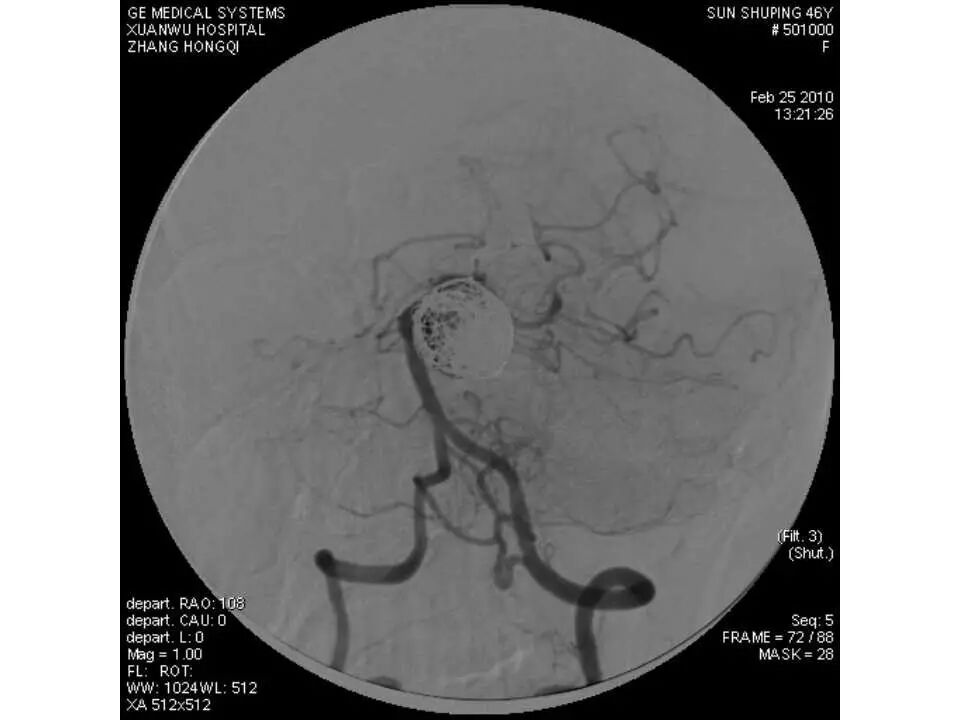

今天为大家分享的是“强生医疗CNV-神经介入专栏”第十五期,由首都医科大学宣武医院何川教授带来的“颅内动脉瘤介入治疗”精彩讲课视频及PPT,欢迎观看、阅读。文章仅代表作者个人观点,如有不同见解,欢迎同道斧正!